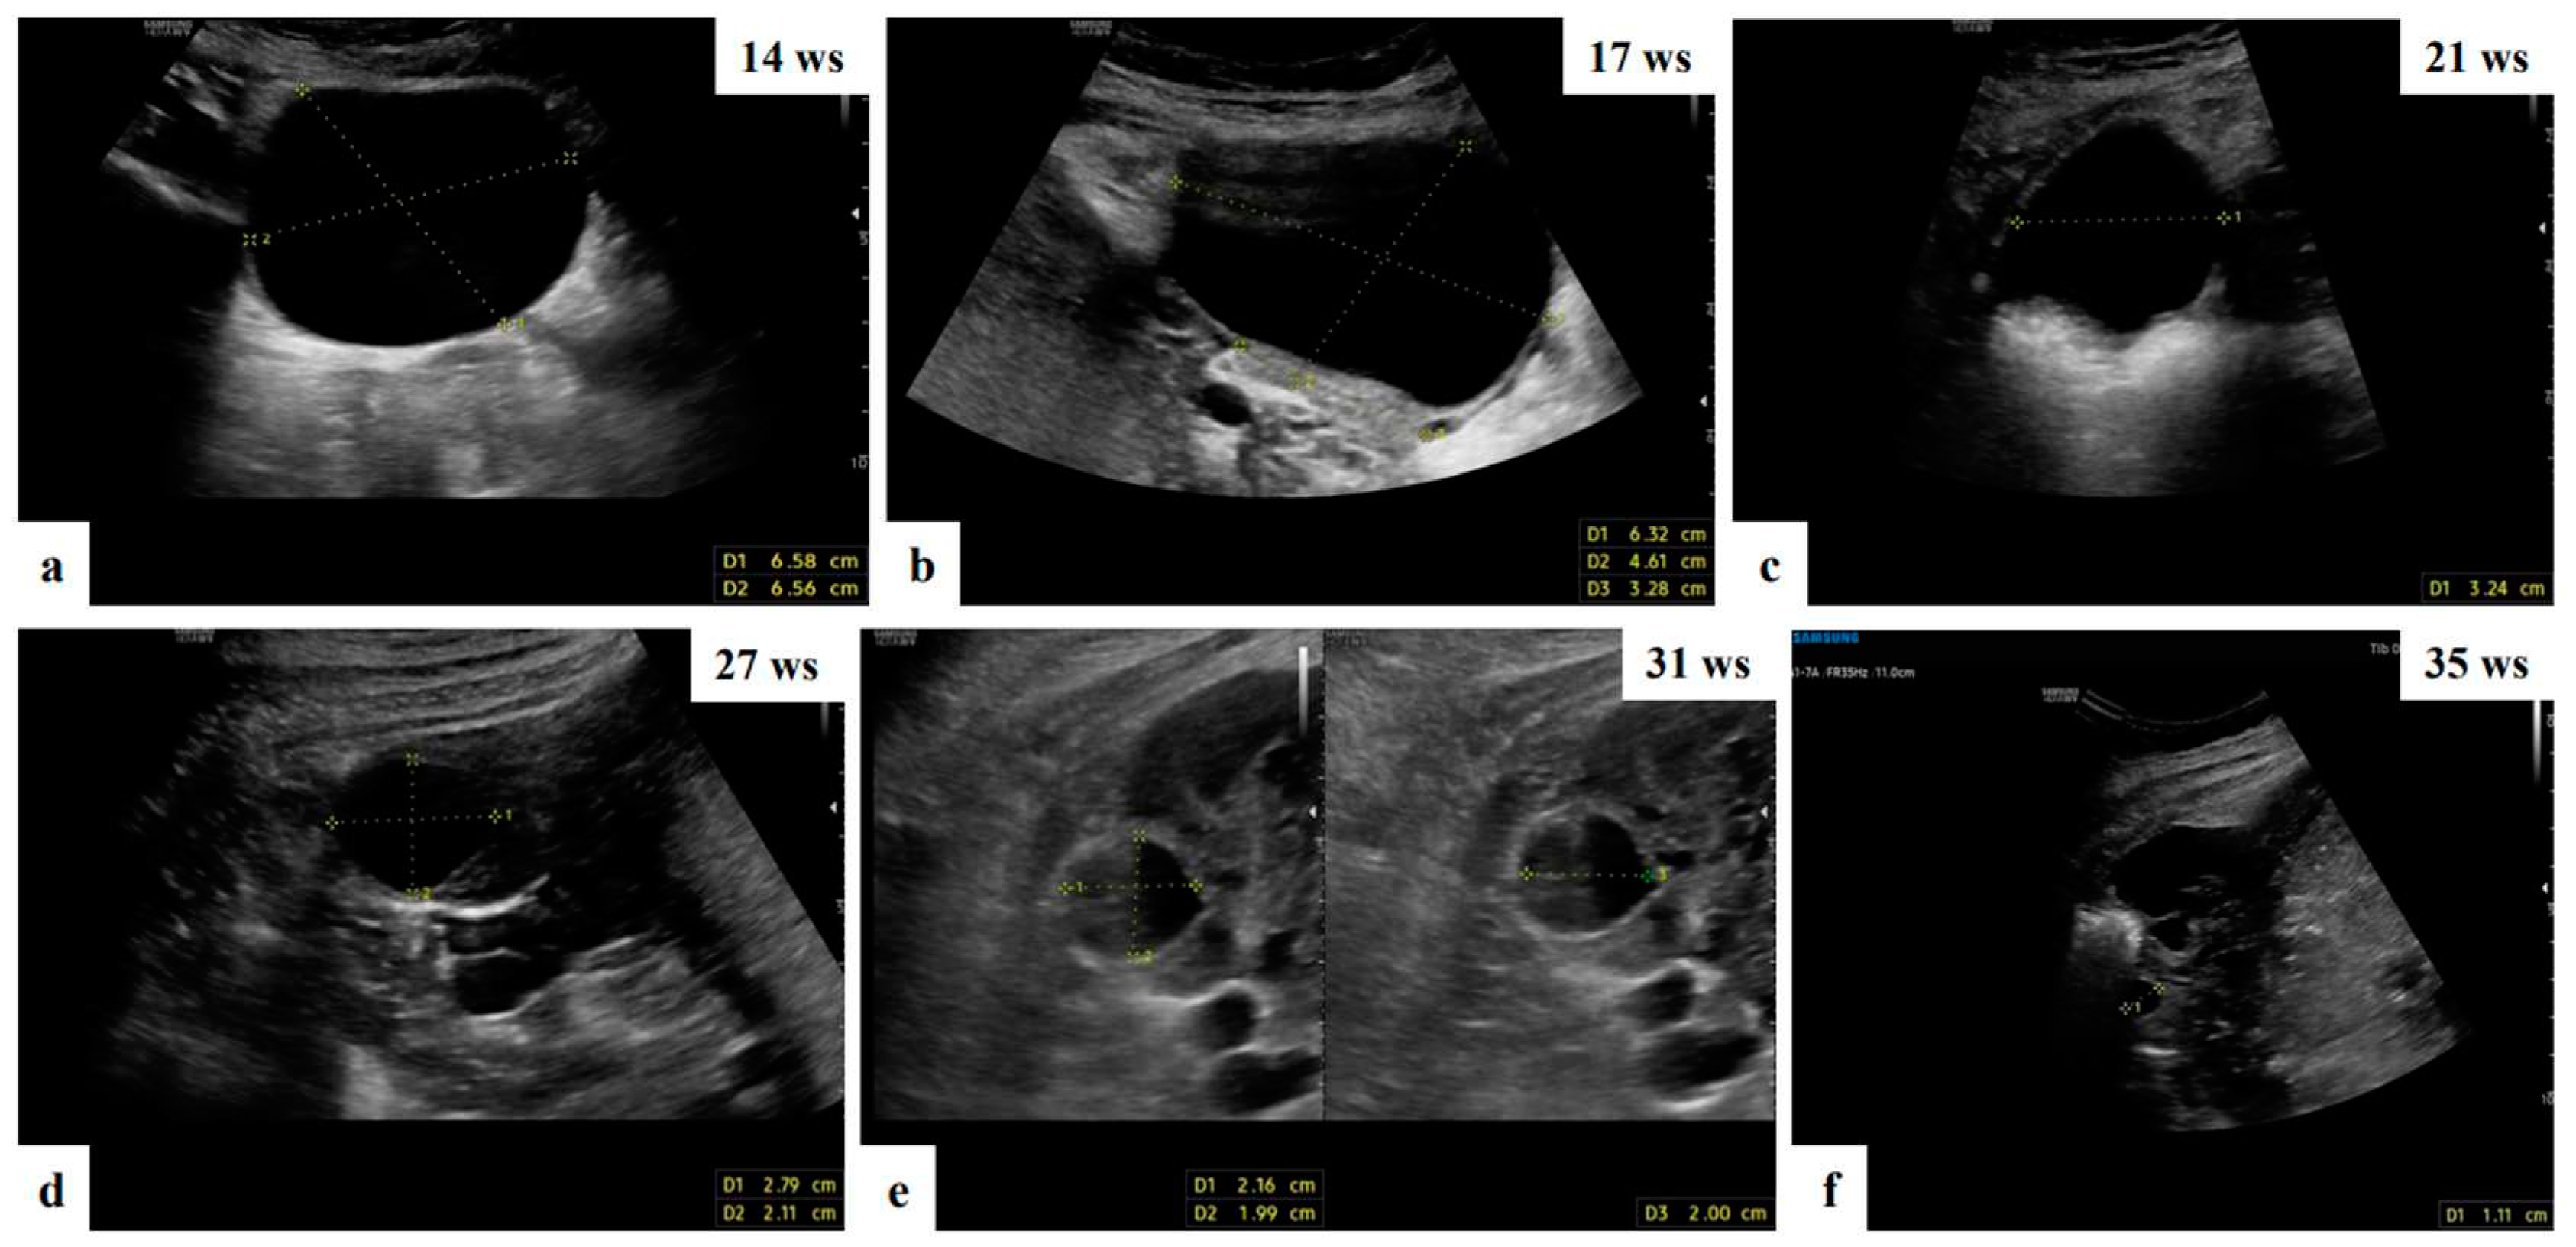

- Mascilini, F.; Moruzzi, C.; Giansiracusa, C.; Guastafierro, F.; Savelli, L.; De Meis, L.; Epstein, E.; Timor-Tritsch I., E.; Mailath-Pokorny, M.; Ercoli, A.; Exacoustos, C.; Benacerraf B., R.; Valentin, L.; Testa, A.C. Imaging in gynecological disease. 10: Clinical and ultrasound characteristics of decidualized endometriomas surgically removed during pregnancy. Ultrasound Obstet Gynecol 2014, 44, 354–360. [Google Scholar] [CrossRef]

- Pateman, K.; Moro, F.; Mavrelos, D.; Foo, X.; Hoo, W.L.; Jurkovic, D. Natural history of ovarian endometrioma in pregnancy. BMC Womens Health 2014, 14, 128. [Google Scholar] [CrossRef]